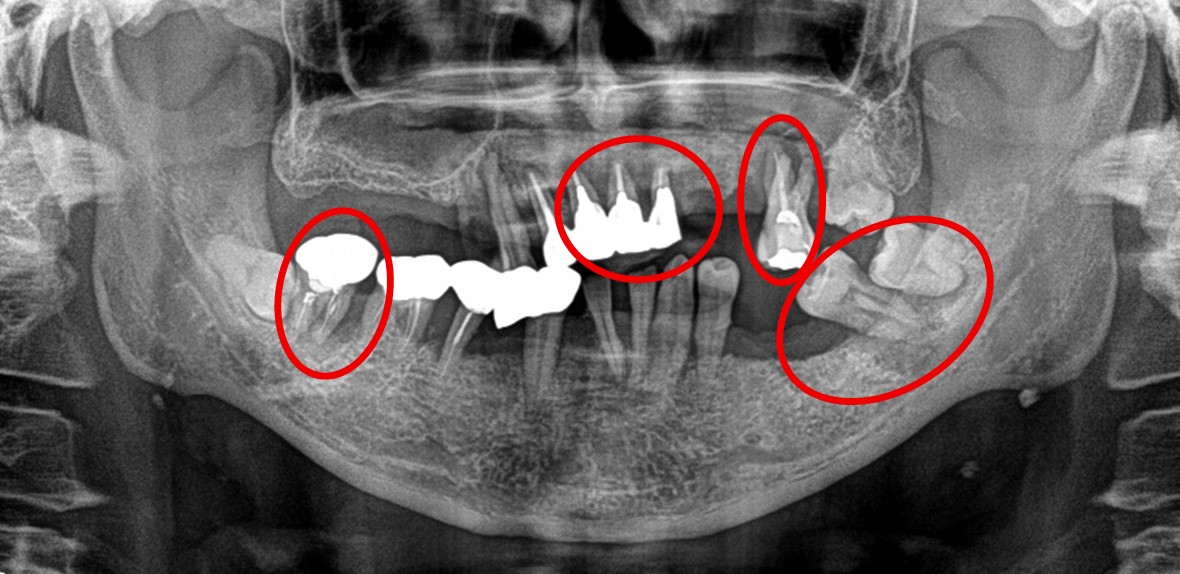

男性Iさん 50代(マグネット式入れ歯)

治療内容

歯周病が進行し深刻な状態でした。保存することができない歯が上4本、下3本ありましたので、抜歯し、残った歯上4本、下7本の歯周病治療を徹底的にし、それらの歯を活用し上下マグネット式総入れ歯を入れました。

Before

赤丸は抜歯しました。上4本、下3本